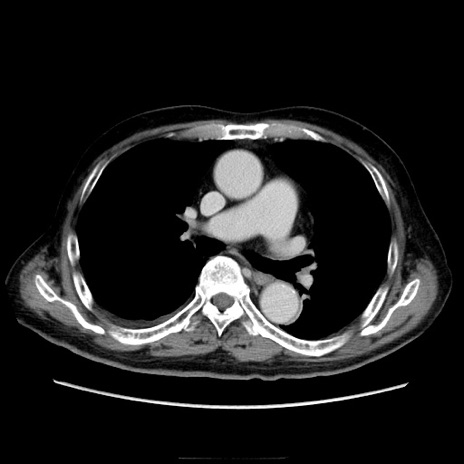

冠状断像